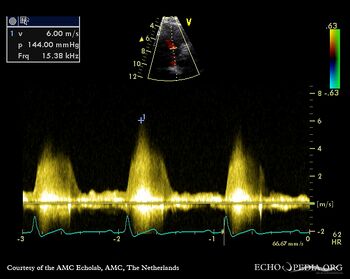

Perimembraneous VSD

PSAX with Color Doppler Continuous-wave Doppler signal of flow through ventricular septum defect

PLAX with Color Doppler Continuous-wave Doppler signal of flow through ventricular septum defect